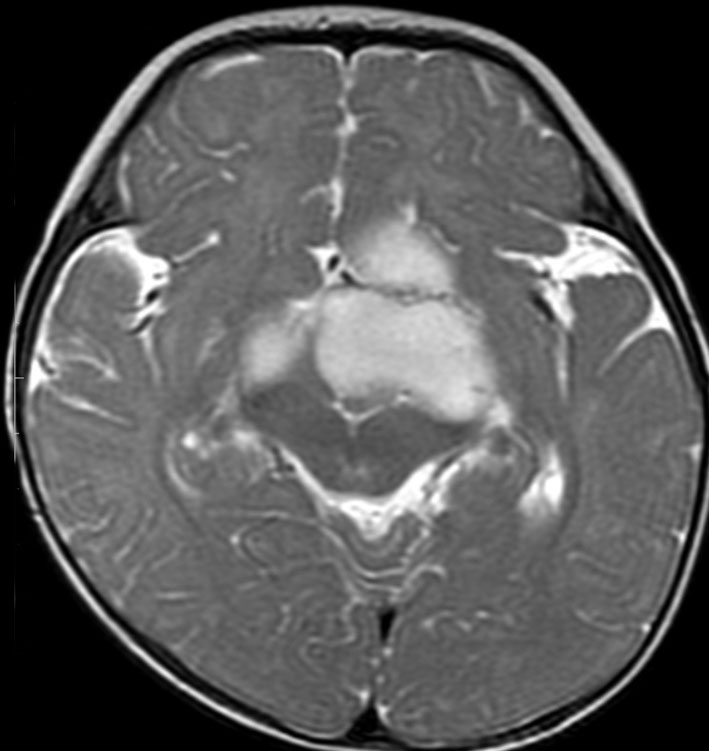

幼児の視路の毛様粘液性星細胞腫です。T2強調画像(左側)で白く高信号に写るのが特徴です。ガドリニウム増強ではまだらになっていますが,均一に真っ白に高信号になることも多いです。乳幼児のものは,ドロドロに柔らかい腫瘍です。

生後7カ月の幼児です。目が揺れるようになり(振り子様眼振)眼科を受診して腫瘍が発見されました。小児脳腫瘍の治療ができる病院へと紹介されました。

1ヶ月後にまたMRI検査がされました。乳児ですから検査にも麻酔が必要です。腫瘍は明らかに大きくなっています。左視神経から視索の腫瘍化が著しいので右側だけかすかに視力が残っているかもしれません。視力は明かりがわかる程度(明暗弁)と評価されました。

こんなことを書くのは悪いことかもしれませんが,まったく馬鹿げた提案です。この画像はどこをどう見ても視路から発生した毛様粘液性星細胞腫です。画像はpathognomonic(日本語で火を見るよりも明らか)です。この小さな子に,全身麻酔をして開頭手術で生検病理診断すれば,それだけで3週間は化学療法の開始が遅れます。その間に明かりも見えなくなってしまう(完全失明する)可能性が高いでしょう。2021年時点でも,開頭手術による生検術は行われていますが,こんな重病の小さな子どもの頭を無用に開くなど,私にはもう理解不能です。